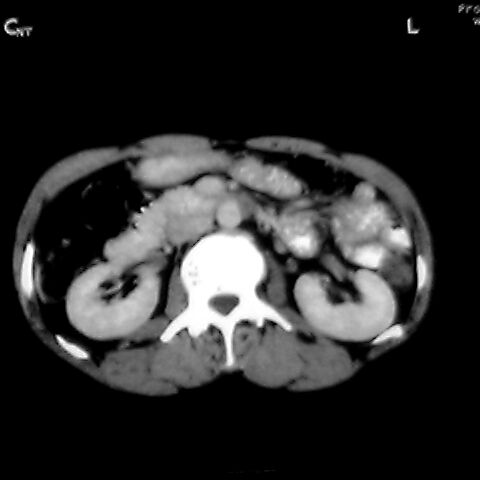

女 48岁 食道癌术前体检发现脾占位。

1肝右下叶小囊肿2右肾上极囊肿或错构瘤3脾脏不典型血管瘤可能性大.

脾脏低密度灶伴钙化,增强化明显,中心见液化坏死灶,强化延时明显。考虑血管瘤。转移瘤待排。

右肾见类圆形低密度影.结合病史.脾及右肾转移性ca可能性大

1,脾血管瘤。2,右肝,右肾小囊肿。